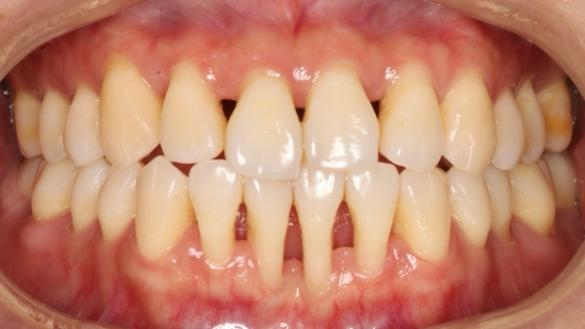

牙龈萎缩:不可忽视的因素

牙周病会导致牙龈和牙槽骨的退缩,这是牙周病进展的结果。当牙龈和骨头萎缩后,牙齿之间的支撑减弱,牙缝也会因此变得更明显。

虽然牙周治疗能够控制和改善炎症,但对已经发生的牙龈萎缩却难以逆转。因此,牙周治疗后,你可能会发现牙缝“变大”了。

牙周炎口内照